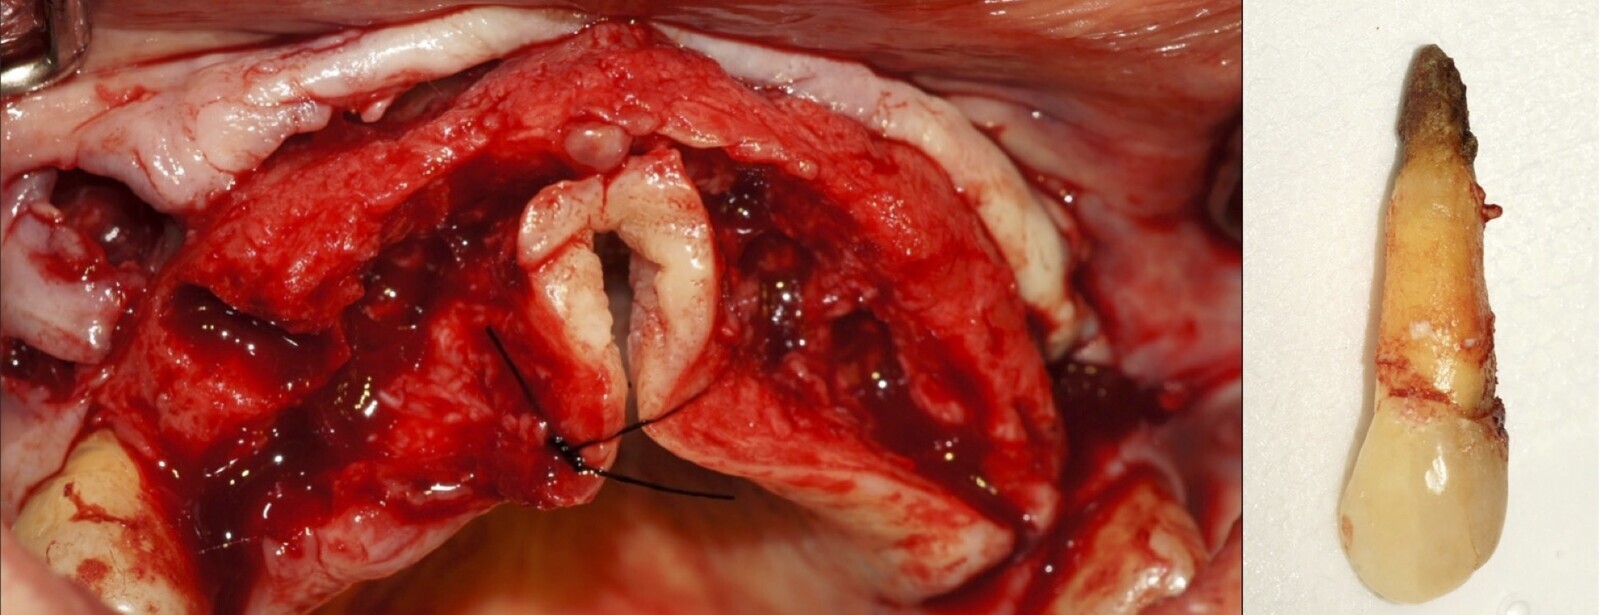

Después de realizado el acceso e identificado el ápice, se procede a la limpieza de la zona con instrumentos manuales y/o con insertos diamantados de parte activa angulada para poder eliminar todo el tejido patológico del perímetro radicular apical y del tejido óseo circundante (Figura 6).

Figura 6. Eliminación mecánica con instrumento manual de tejido granulomatoso (a, b). Limpieza peri radicular del tejido dentario apical y óseo (c, d).

Figura 8. Excéresis (a) y curetaje apical (b) que garantice una zona limpia para la terapia endodóntica apical.